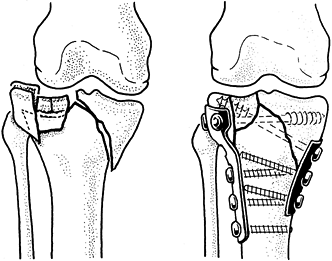

wire alone, as in a transverse fracture of the patella in which an

irregular fracture line allows perfect reduction by interdigitation of

the fracture surfaces (Fig. 11.11). In most

situations, however, axial rotational stability cannot be obtained

without the addition of two parallel, longitudinally placed K-wires (Fig. 11.12).